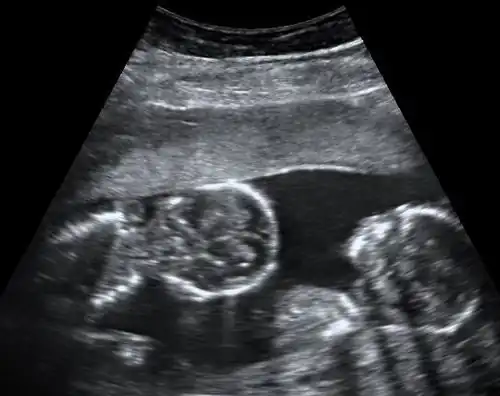

Diagnosis

By performing an obstetric ultrasound at a gestational age of 10–14 weeks, monochorionic-diamniotic twins are discerned from dichorionic twins. The presence of a "T-sign" at the inter-twin membrane-placental junction is indicative of monochorionic-diamniotic twins (that is, the junction between the inter-twin membrane and the external rim forms a right angle), whereas dichorionic twins present with a "lambda (λ) sign" (that is, the chorion forms a wedge-shaped protrusion into the inter-twin space, creating a rather curved junction).[4] The "lambda sign" is also called the "twin peak sign". At ultrasound at a gestational age of 16–20 weeks, the "lambda sign" is indicative of dichorionicity but its absence does not exclude it.[5]

In contrast, the placentas may be overlapping for dichorionic twins, making it hard to distinguish them, making it difficult to discern mono- or dichorionic twins on solely the appearance of the placentas on ultrasound.